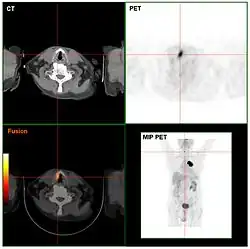

Scans of a bronchial tumor taken using CT, PET, PET-CT, and MIP PET

Computed tomography (CT) and positron emission tomography (PET) scans are similar to MRI, but rely on different imaging techniques (X-rays and ionizing radiation, respectively). A variation of CT known as contrast CT also requires the subject to take in a contrast medium called a radiocontrast (typically by oral consumption, enema, or injection). Positive radiocontrast agents such as barium sulfate increase the body's X-ray attenuation, causing the tissue containing them to appear whiter in the X-ray image. Meanwhile, negative agents such as carbon dioxide gas allow X-rays to pass through them easily, causing the tissues containing them to appear darker.[49]

Like magnetic resonance imaging, CT scans use numerous methods to display and measure data, including sequential CT (where the CT table steps from location to location), spiral CT (where the entire X-ray tube is spun around the subject), and electron beam tomography (where only the electron paths are spun using deflection coils). PET scanners don’t have quite as much hardware variation and instead use different radiotracers depending on what the imaging target is. Note that radiotracers are distinct from radiocontrasts; the former relies on radioactive decay to trace its path while the latter is absorbed into specific tissue and affects that tissue's X-ray attenuation. Because these methods are not mutually exclusive, PET and CT can be performed simultaneously using PET-CT scanners, which are used for the majority of modern PET scans.[50]

Either or both of these methods can be used in conjunction with maximum intensity projection (MIP) to convert the scan data into a 3D image. This can be difficult to accomplish due to artifacts created by respiration and bloodflow, which can appear as abnormalities to an untrained eye; however, it's possible to distinguish these artifacts from real disease so long as careful attention is paid to them.[51] When done well, CT and PET scans taken with MIP are excellent for identifying small abnormal tissue growths, especially in the lungs. Scans taken with MIP for this purpose tend to have higher significance than averaged images created with traditional CT.[52]

MIP imaging is also used with magnetic resonance angiography, and research has indicated that it could feasibly be used with MRI.[53] At least one study has shown that MIP MRI actually significantly outperforms single-slice MRI when used by neural networks to classify lesions based on malignancy.[54]